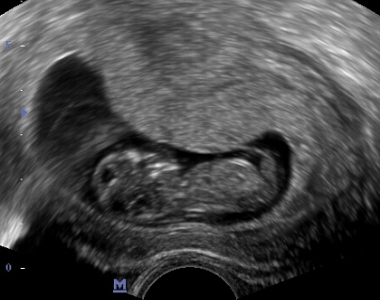

Objednala jsem se ke své lékařce a šla k ní 8. dubna, to už jsem byla v 6tém týdnu. Za dva týdny na další kontrole už krásně bilo srdíčko. Lékařka mi doporučila objednat se do Olomouce na prvotrimestriální screening (kombinace odběru krve a ultrazvuku). Na ten jsem jela ve 12tém týdnu 18. května. Odběry krve i ultrazvuk dopadly na jedničku, i když andílek moc spolupracovat nechtěl a ultrazvuk vyšel až na třetí pokus. A já si odnášela fotečku a báječný pocit, že je andílek zdravý a krásně prospívá. Rovnou si mě tam objednali na kardiologický ultrazvuk srdíčka miminka a na druhotrimestriální screening.

Potom mi ale pan doktor řekl, že je tam sice špatně vidět, ale že tam je problém. Hlavička má tvar citronu, nožičky a ručičky délkou odpovídají 14-15 týdnu a já byla ve 22 tt. Hrudníček byl oproti bříšku maličký ve tvaru hrušky a skoro celý jej vyplňovalo srdíčko. Na plíce nezbývalo moc místa, takže byly jen hodně maličké. Bylo podezření na kostní a plicní dysplázii. Řekl mi, že je potřeba udělat na genetice odběr plodové vody a další ultrazvuk. Byla jsem úplně v šoku. Ještěže tam se mnou byla kamarádka, která shodou okolností pracuje ve FN Olomouc. Hned ráno na druhý den mi volala, že mi domluvila schůzku s panem profesorem Šantavým z genetiky na čtvrtek ráno.

Manžel si vzal v práci volno, já si ve středu byla pro neschopenku v práci a ve čtvrtek ráno jsme byli v Olomouci. Pan doktor mi dělal skoro dvouhodinový ultrazvuk a pak řekl, že je to hodně špatný, že pokud by andílek zvládl přežít do porodu, tak po porodu by to už nezvládl kvůli nevyvinutým plícím. V ten čtvrtek jsem se i dozvěděla, že to bude vysněný chlapeček. A jeho nemoc se jmenuje thanatoforický dwarfismus.